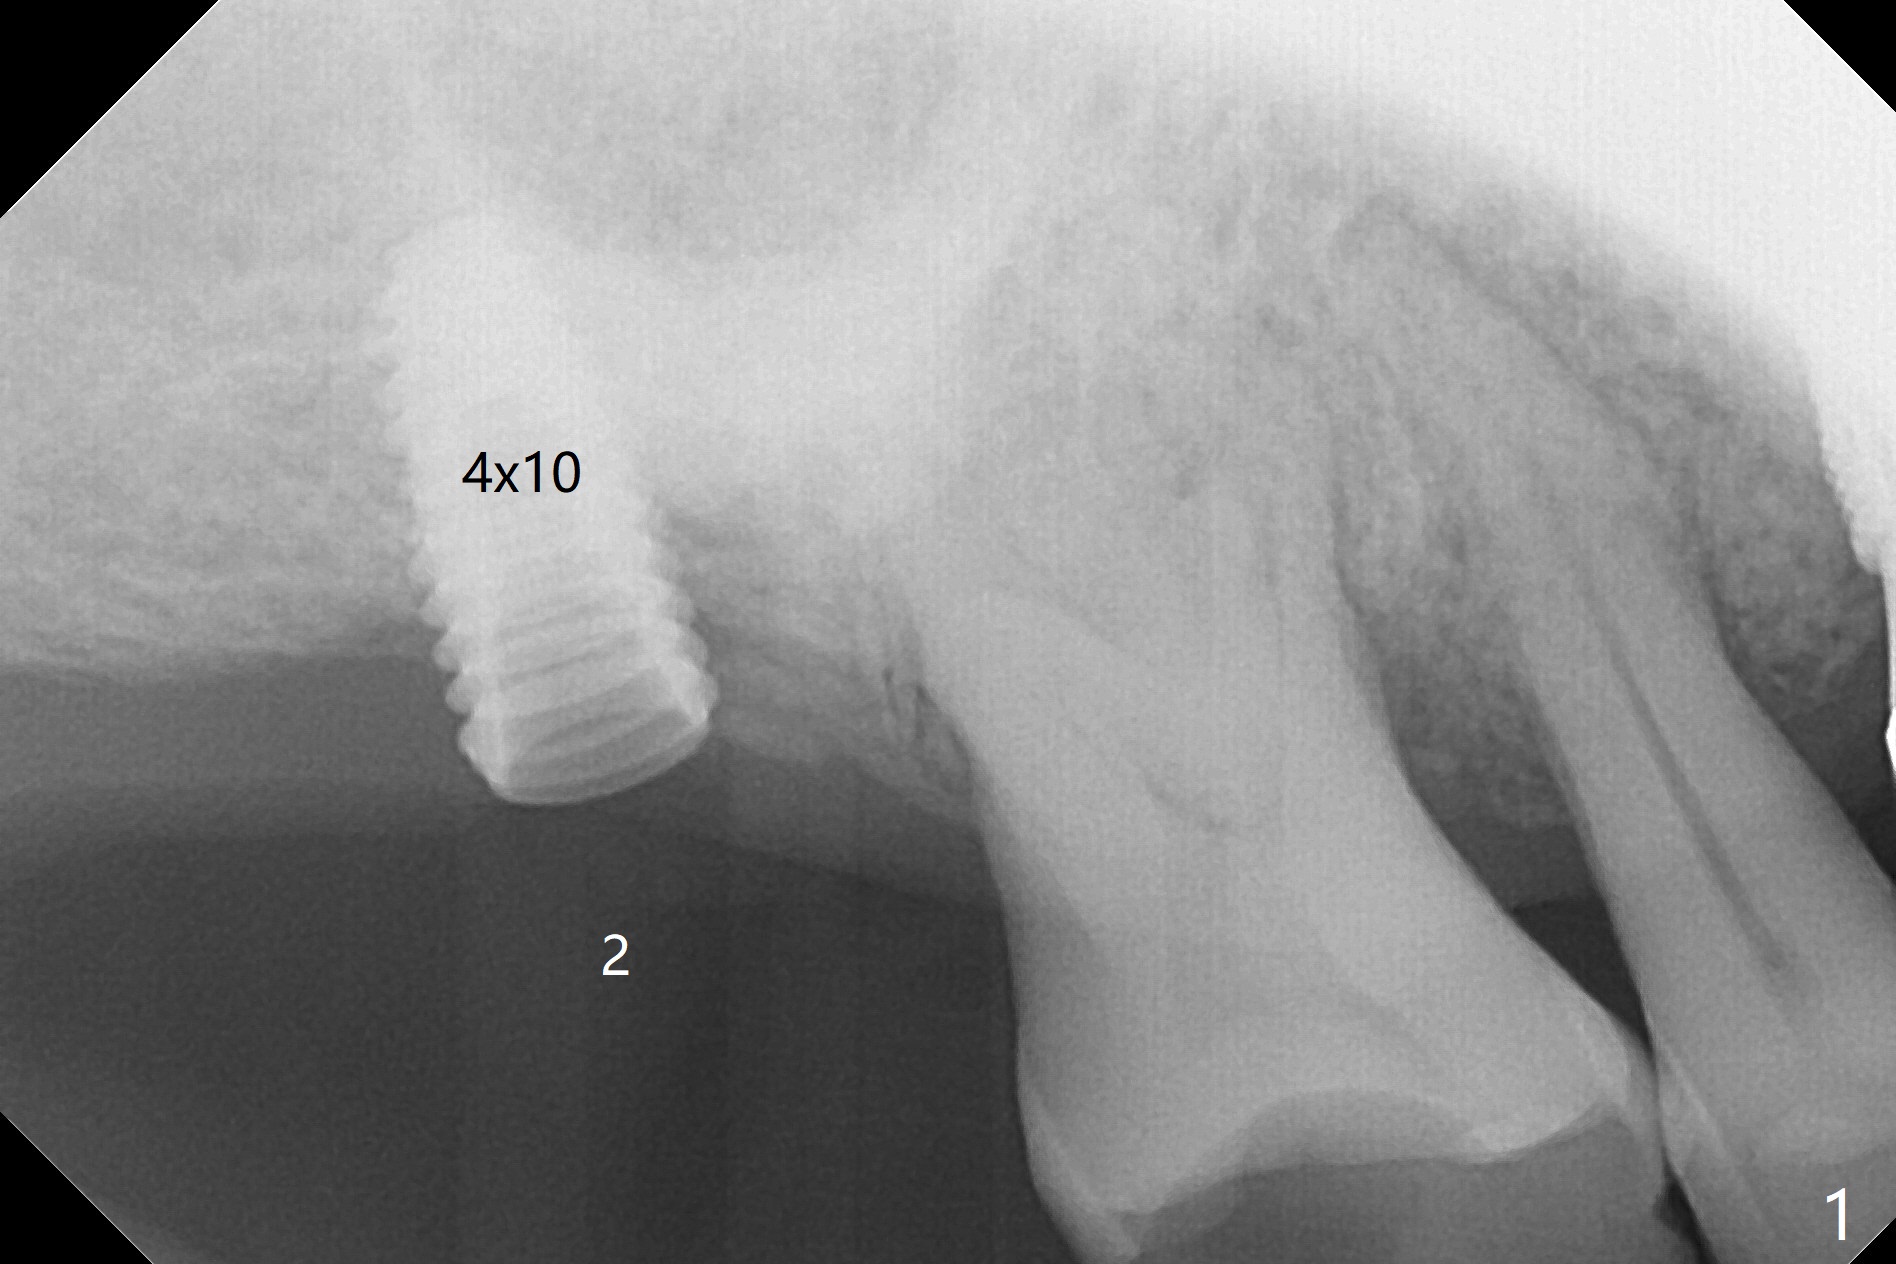

Two things happen immediately before this surgery. A SM implant is found to fail related to bruxism and poor oral hygiene, ~ 5 years in function; a UF implant will be used instead. DIO Sinus Approach Kit has not been autoclaved; therefore the free-hand one has to be used with caution. In fact the procedure goes on apparently smoothly in spite of the fact that the patient with medical knowledge is nervous about the risk of sinus lift. After 4.0x8.5 mm Neo Navi drill with 12 mm offset, the 3.6 mm sinus safety drill is used from 7 to 9 mm in length, followed by water balloon, PRF membranes (x2) and mixture of autogenous bone graft and allograft and 4.5x10 mm dummy implant (Fig.1). The definitive implant is placed with satisfactory stability (Fig.2), but a 6.5x7(4) mm healing abutment is close to the mesial crest (*). The former is reloaded following 6.0 mm Bone Profile Drill (Fig.3) and then is changed to a 6x6 mm IS one. The patient reports nasal hemorrhage immediately returning home, but there is no similar episode a few hours later. Re-analysis of preop (Fig.4) and immediate postop (Fig.5) CT shows that water balloon technique in fact swells the sinus membrane (M) instead elevating it. It is safe to place more bone graft (Fig.5 *). There is pain when the 6x6 mm healing abutment is being removed nearly 5 months postop (Fig.6.7). The patient complains of mild sinus discomfort, although panoramic X-ray does not show abnormality (Fig.8). He will return for recheck for implant stability (low bone density) before impression 2-4 months later.